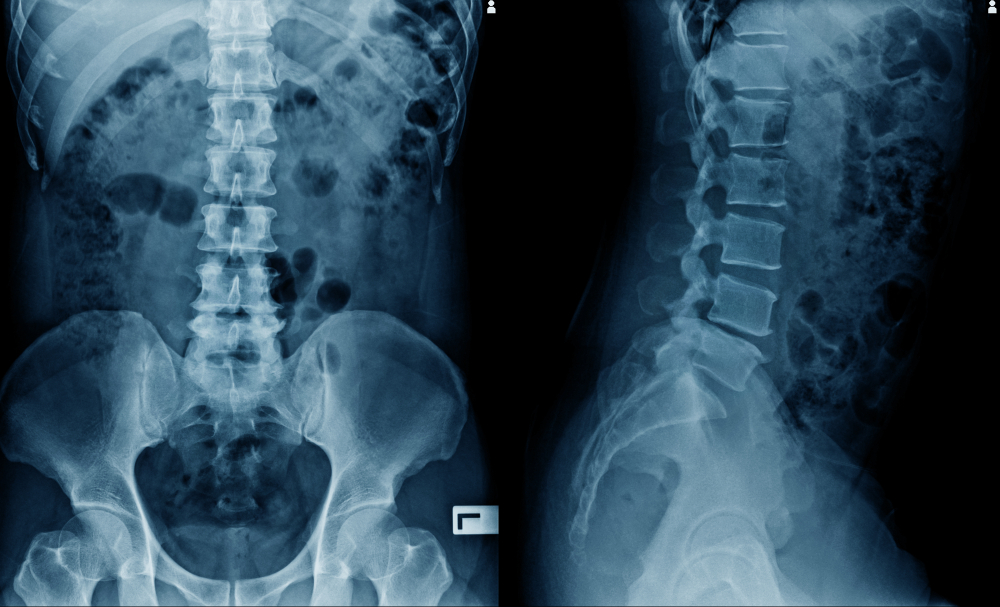

Lumbosakralinės stuburo rentgeno nuotraukos atliekamos siekiant įvertinti apatinės nugaros dalies būklę. Ši procedūra leidžia gydytojui detaliai pamatyti juosmeninę stuburo dalį bei ją supančius audinius.

Juosmeninę stuburo dalį sudaro penki slanksteliai, kurie remiasi į kryžkaulį – tai tvirta, trikampio formos kaulinė dalis ties dubens dugnu. Po kryžkauliu yra uodegikaulis, o viršuje – krūtinės stuburas. Šioje srityje taip pat eina didelės kraujagyslės, nervai, sausgyslės, raiščiai bei kremzlės.

Lumbosakralinio stuburo rentgenas daromas ligoninės radiologijos skyriuje arba specializuotoje klinikoje. Tyrimo metu pacientas paprastai paguldomas ant specialaus stalo aukštielninkas. Virš nugaros gydytojas ar specialistas pastato didelę kamerą su metaliniu rankiniu, kuri sukuria stuburo nuotraukas.

Procedūros metu gali būti prašoma keisti kūno padėtį – atsigulti ant šono, pilvo ar net atsistoti, jei reikia įvairių stuburo vaizdų skirtingais kampais. Svarbiausia – išlikti visiškai ramiai ir sulaikyti kvėpavimą, kol daromos nuotraukos. Tai padeda gauti kuo tikslesnius vaizdus be judesių iškraipymų.